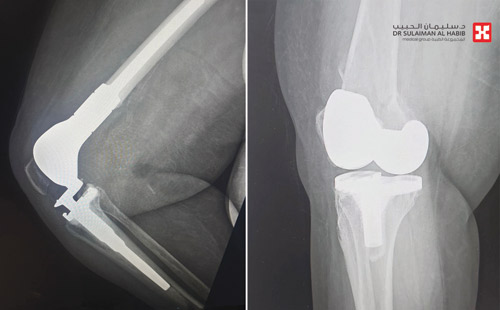

وقال أن السيدة حضرت إلى المستشفى وهي تشتكي من آلام حادة وتورم بالطرف السفلي الأيمن، مع عدم القدرة على الحركة والتحمل، إضافة إلى أمراض مزمنة كالشريان التاجي وداء السكري وارتفاع ضغط الدم، وقد أظهرت صور الأشعة الطبية كسراً في نهاية عظم الفخذ حول المفصل الصناعي، وتبين عدم قابلية الكسر للتثبيت بالصفائح أو البراغي، بالنظر إلى هشاشة عظام السيدة وتقدم عمرها، فتم اعتماد خطة علاجية تناسب الحالة، وأجريت لها عملية جراحية تم فيها استبدال الجزء السفلي من عظمة الفخذ، في تدخل جراحي استمر «4» ساعات، وتكلل ولله الحمد بالنجاح التام، ونقلت المريضة إلى جناح التنويم.

وأضاف د. شبو المريضة بقيت منومة في المستشفى لمدة «7» أيام تحسنت خلالها صحتها، ومن ثم غادرت المستشفى وهي بصحة جيدة، ولاحقاً استعادت قدرتها على الحركة وتخلصت من كافة الأعراض، وعادت تمارس حياتها بصورة طبيعية. وأوضح أن من مزايا هذا الإجراء توفير ثبات ميكانيكي فوري، والسماح بالحركة المبكرة وتحمل الوزن مباشرة، وتقليل المضاعفات الناتجة عن عدم الحركة، خصوصا لدى المرضى المسنين وذوي الأمراض المزمنة.